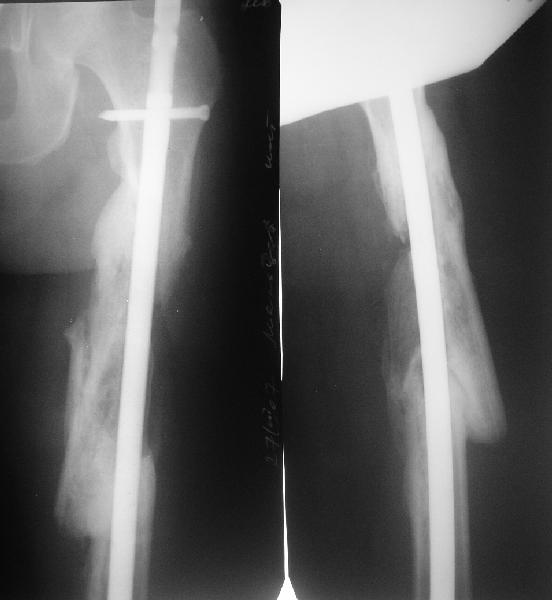

Привет из Нижнего Новгорода! К нам поступил пациент 25 лет с закрытыми переломами обеих бедренных костей, прошел месяц после травмы. Слева - внутрисуставной перелом, поэтому выбор здесь очевиден, открытая репозиция, стабильная фиксация, скорее всего LCP DF, а справа - мнения учёных, как говорится, разошлись. Лично я, как лечащий врач, за закрытый интрамедуллярный остеосинтез DFN. Со мной согласна половина коллектива, другая - за интрамедуллярный остеосинтез (DFN,UFN) но с открытой реопозицией, поскольку при закрытой методике все осколки останутся где-то сбоку, получится дефект и вдруг не срастется!Философский вопрос: что лучше - красивая рентгенограмма или сохранение кровоснабжения? Очень важно мнение коллег! Смирнов Алексей

Мы бы не стали открывать, такие переломы срастаются, хотя бы и с краевым дефектом. То есть если удалять стержень потом, то сильно попозже обычного. В приложении пример. Сразу после операции и через 11 мес. Понятное дело, пациент к тому времени давно и не хромал, и функция колена была полная.